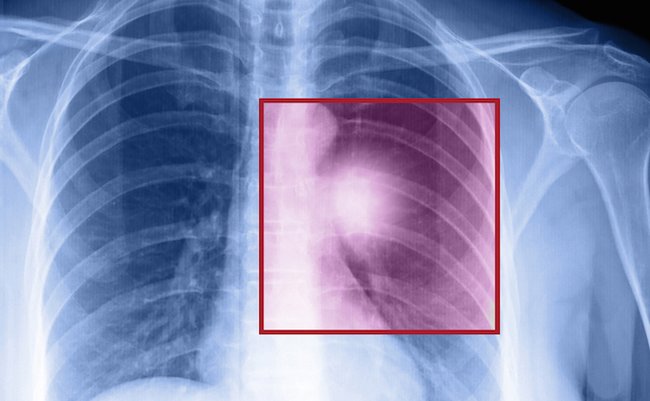

今回、人体に無害な光(近赤外線)を当ててがん細胞を壊す新しい治療法を米国立保健研究所(NIH)の小林久隆・主任研究員らが開発し、患者で効き目を調べる治験(臨床試験)を近く始める。光を受けると熱を出す特殊な化学物質をがん細胞の表面に結びつけ、がんだけを熱で狙い撃ちする。

近赤外線は放射線や陽子線と違い正常細胞には無害であるし、取り扱いが容易である。標的となるがん細胞に対しては抗体を使い、がん細胞に結びついた抗体は近赤外線に反応してがん細胞を効率的に攻撃するなどの工夫を取り入れた。